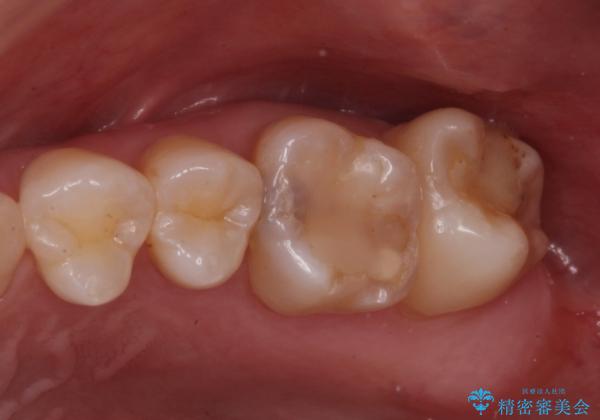

奥歯の治療の劣化が気になる。ザラザラしている

- 奥歯がザラザラして欠けている気がするとの事で来院。

古いプラスチックの詰め物がされていて、少し欠けていました。

拡大鏡下で古いプラスチックを除去して虫歯がないことを確認して

e-maxインレーにて治療しました。

白い詰め物が入り、ザラザラもなくなりました。

一つ手前の古いプラスチックで治療されている歯も現在詰め物にやりかえを検討中です。